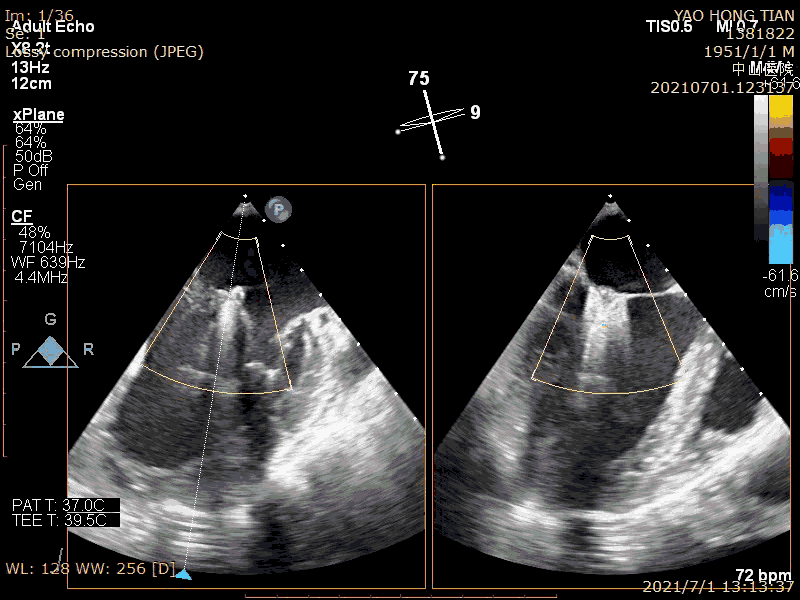

Final effect (mild regurgitation), maximum/mean pressure difference: 4/1mmHg

Among the etiological components of mitral regurgitation, functional regurgitation is more common, which is 3-4 times that of organic regurgitation (Am Heart J. 2018; 203:39-48.). Atrial functional mitral regurgitation (AFMR) is also very common in functional regurgitation, and the author estimates that it can account for 40%. The results of this case show that ValveClamp has a good effect on AFMR, with simple operation, catheter operation time less than 20 minutes, total operation time less than 50 minutes, and mild regurgitation after operation. It is particularly mentioned that the regurgitation range in this case reaches 13mm, and the regurgitation is multi-beam. One ValveClamp clip achieves a perfect effect, while other products may require 2-3 clips, which fully reflects the design advantage of ValveClamp of "treating large problems with small means". Using only a single clip can reduce the difficulty and time of the operation and the cost of consumables.